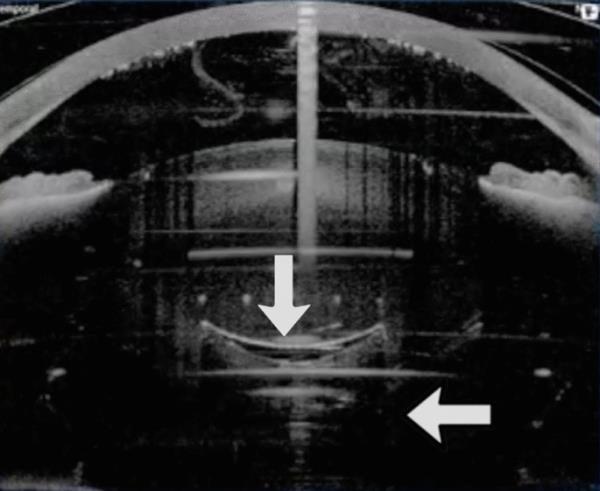

当晶状体核非常坚硬,晶状体后皮层出现大气泡时,后囊膜发生瞬间后侧移位。体积的突然增加不能使上面的立晶状体移位,而使后部的后囊移位。斑点能量高于要求和晶状体硬度有利于这种机制,这种机制似乎不是使后囊膜的一部分而是全部移位(图3,视频3)。由于整个后囊膜移位,后囊膜破裂的风险相对较低。这种形成在硬白内障中尤其明显,因为硬晶状体材料吸收部分气体的能力很小。此外,复杂的前透明体/玻璃体比尚未碎裂的硬核和大核对气体扩张的阻力更低,从而允许后囊移位。

图3

大气泡导致晶状体后囊膜震荡,伴有短暂的后囊膜移位,尤其是中央部分(白色箭头)。另见补充资料中的视频3